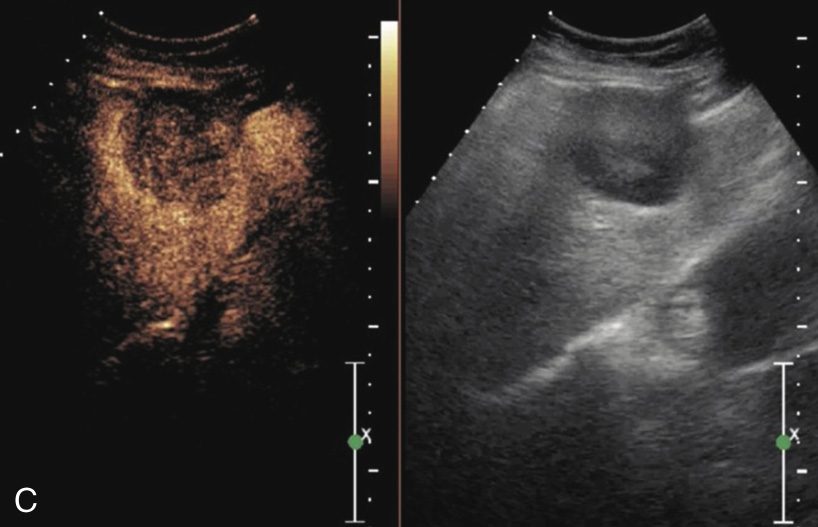

(6)超声造影:表现为“快进快出”,即注射造影剂后动脉期病灶呈均匀或不均匀高增强,门脉期或延迟期呈低增强(图1-7-3)。

图1-7-3 肝细胞癌超声造影图像

A.动脉期呈不均匀高增强;B.动脉期16s达峰;C.门脉期造影剂消退呈低增强